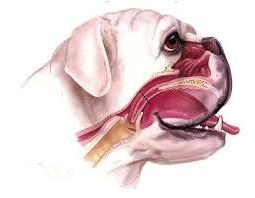

How vets diagnose muscle, bone and joint problems

A good work-up usually starts with careful observation and a hands-on examination, which may include checking joint range of motion, muscle symmetry, and specific areas of tenderness. From there, vets choose tests based on what they find and what your dog can tolerate.

Imaging is often central. X-rays are commonly used to assess bones and joints, including evidence of arthritis. When soft tissue injury is suspected, or when the picture is more complicated, advanced imaging such as CT or MRI can be helpful. For chronic pain, vets also pay close attention to how your dog behaves at home, because pain can be situational and subtle in a clinic setting.3, 4